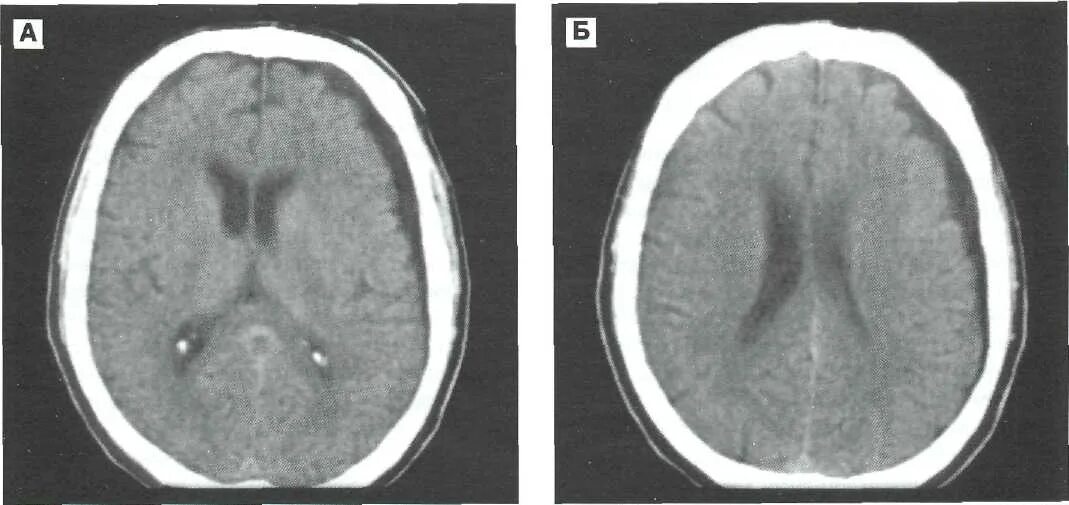

Гематома лобной